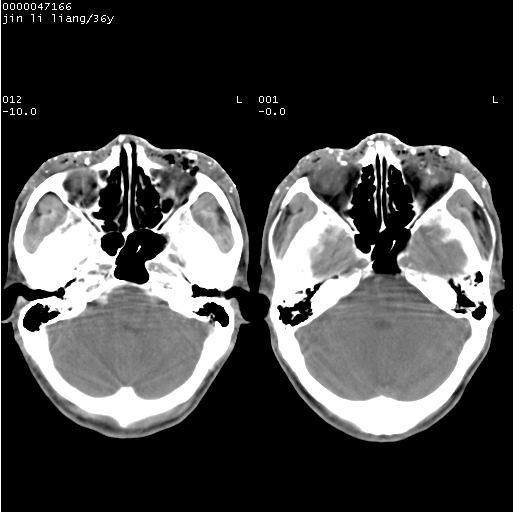

患者 男,36岁。头面部“土炮”炸伤。pe:面目全非,伤口流血不止。

临床诊断:头面部外伤。

颅脑ct轴位平扫(层厚、层距均为10mm),图像如下:

左眼球内容物浑浊其内见气体影,头面部异物.

左眼球破裂并异物,眶周、额顶部头皮及软组织挫伤并异物

左眼球破裂积气并异物,眶周、额顶部头皮及软组织挫伤并异物!

迎面一炮,满脸开曝。额顶部头皮及软组织挫伤并异物,左眼球破裂积气并异物,典型的面目全非,惨不忍睹。

左侧眼球破裂积气异物存留   颜面额部多处软组织挫伤并异物!

左眼球破裂积气并异物,眶周、额顶部头皮及软组织挫伤并异物,右侧眼环前内分异物

额顶部头皮及软组织挫伤并异物,左眼球破裂积气并异物。可怜

1左侧眼球破裂并积气,球内、框内异物。

2额部顶部软组织伤。